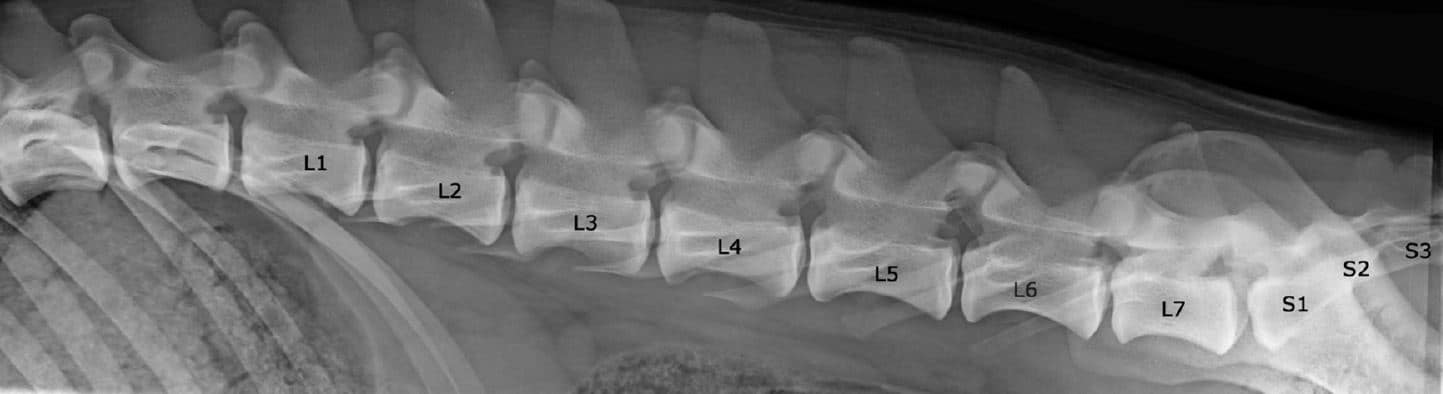

normal spine

A normal canine spine consists of 7 cervical (C1-7), 13 thoracic (T1-13), 7 lumbar (L1-7) and 3 sacral vertebras (S1-3) resulting the total of 30 vertebras. Calculation starts from first thoracic vertebra (T1). The number of caudal vertebras (CD) vary.

Sacrum connects the lumbar spine to pelvis. It’s a part of the pelvis and it lies between the lumbar spine and tail. Sacrum is strong, triangular in shape and it sits between the hip bones. Normal sacrum consists of three fused vertebral segments; S1, S2 and S3.